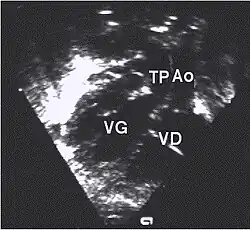

- Les coupes échographiques les plus utiles à cette fin sont :

- La coupe parasternale gauche grand axe : elle montre que le vaisseau issu du ventricule gauche (le plus postérieur) se dirige anormalement vers l'arrière et se bifurque précocement. C'est donc le tronc pulmonaire et non l'aorte comme normalement.

- Les coupes sous costales qui montrent bien le trajet parallèle des gros vaisseaux et leur inversion. Cet examen permettra d'éliminer en particulier un retour veineux pulmonaire anormal total bloqué qui aurait pu rendre compte de l’hypervascularisation pulmonaire sur la radiographie des poumons.